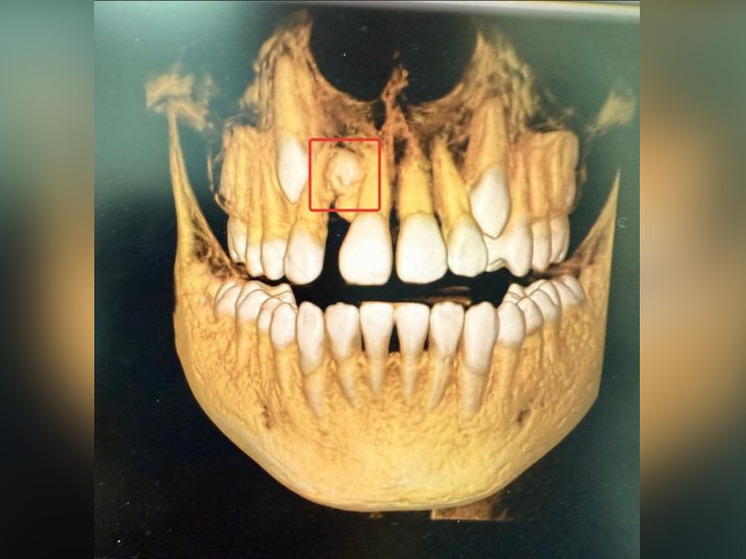

В столице Башкирии врачи стоматологической поликлинике №17 удалили сверхкомплектный зуб 13-летнему школьнику.

Как сообщили в минздраве республики сообщили, что такая аномалия встречается в одном из 1000 случаев. Ребенок обратился к ортодонту с жалобами на эстетические проблемы. На КТ врачи обнаружили лишний зуб в верней челюсти, между центральным и боковым резцом.

Аномалия может вызвать проблемы с речью, смыканием челюсти, вызывать кариес, проблемы с деснами и влиять на форму лица. Врачи удалили сверхкомплектный зуб и провели ребенку ортодонтическое лечение.